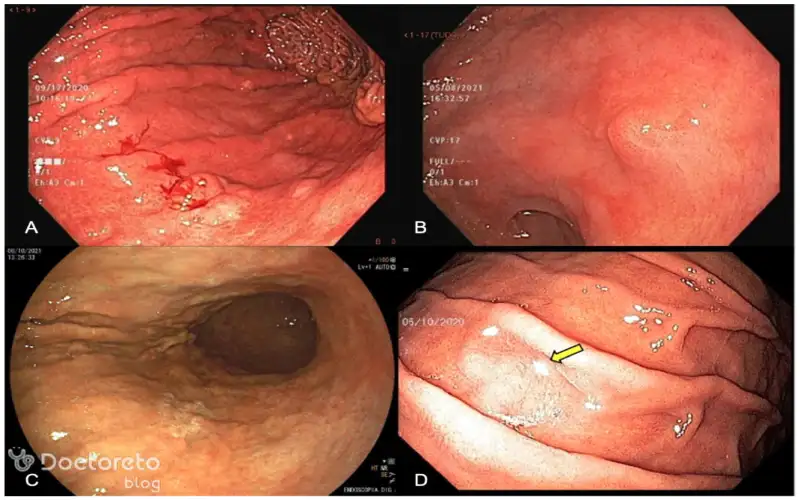

عکس آندوسکوپی سرطان معده خوش خیم

آندوسکوپی یکی از مهمترین روشهای بررسی داخل معده است؛ بهویژه برای مشاهده مستقیم رشد و برداشت نمونه (بیوپسی). در تومورهای خوشخیم، مشاهده مستقیم از طریق آندوسکوپ کمک میکند تا پزشک ماهیت ضایعه را ارزیابی کند. عکس ادامه نشاندهنده اندوسکوپی از ضایعات معده است.